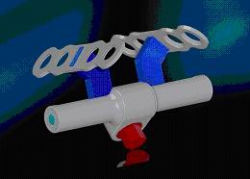

Modern therapy methods, such as distraction osteogenesis, are routinely used and also represent a research focus of the clinic (Magdeburg Palatal Distractor).